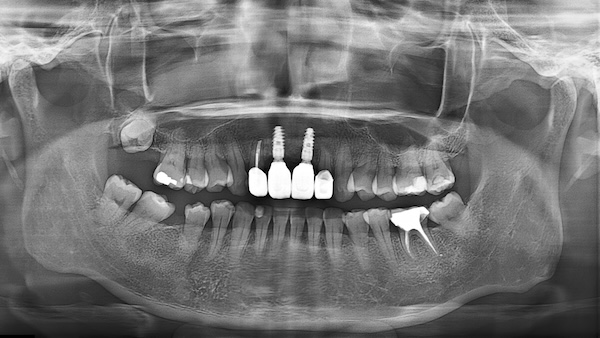

After

嚴選Straumann植體品牌讓美麗笑容,不必再等待

謝小姐在這次植牙手術中,選擇了來自瑞士頂級品牌Straumann植體,即使面臨骨質不足的挑戰,我們透過補骨與補肉手術,搭配Straumann獨家的SLActive®表面技術,大大縮短了癒合時間。

傳統植牙可能需等待3~6個月,

而Straumann植體最快3~4週就能完成癒合,

讓假牙迅速裝載,笑容與功能同步回歸!